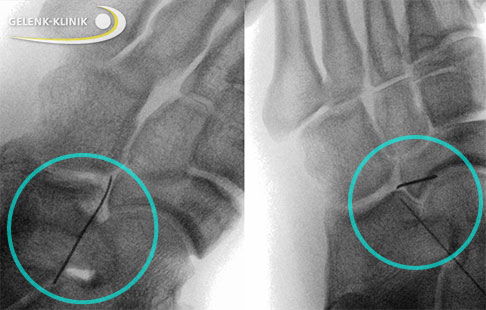

Röntgenaufnahme während der minimalinvasiven Operation einer Coalitio calcaneonavicularis bei einem Jugendlichen mit geschlossenen Wachstumsfugen. Unter Bildwandlersicht wurde eine Nadel im Bereich der Verwachsung zwischen Kahnbein und Fersenbein platziert. Die Abtragung der Koalition erfolgte endoskopisch. © Gelenk-Klinik

Neben der klassischen offenen Operation setzen die Fußspezialisten der Gelenk-Klinik vor allem minimalinvasive Operationsverfahren ein. Diese arthroskopische Operation über kleine Hautinzisionen ist schonender für das Gewebe und die Komplikationsrate ist geringer.

Der Spezialist entfernt die Koalition endoskopisch unter Kamerasicht. Die genaue Lokalisation der Verwachsung prüft der Operateur während des Eingriffs mithilfe von Röntgenuntersuchungen durch einen Bildwandler. Der Bildwandler stellt die entsprechende Körperregion in Echtzeit auf einem Monitor dar. Der Operateur kann so Befunde und Operationsergebnisse in Echtzeit beurteilen.

Während er die Vollständigkeit der Abtragung bei der offenen Operation über den Hautschnitt ertasten kann, überwacht er die komplette Resektion beim minimalinvasiven Verfahren anhand der Diagnostik mit dem Bildwandler.